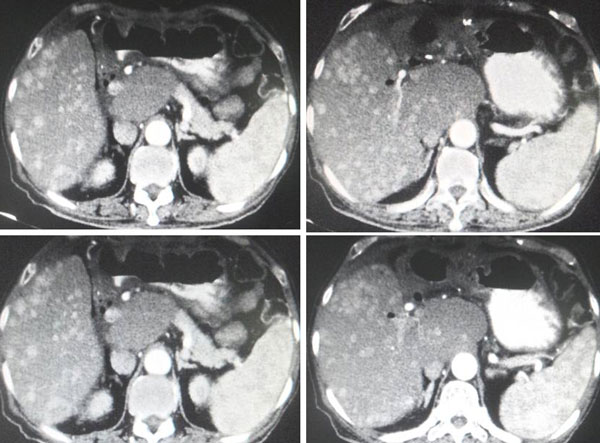

A triphasic CT scan of liver done in July 2015 confirmed:

- Irregular liver surface. Hypodense lesions are seen at both liver lobes, the largest is at segment 7 measures 1.2 cm. These lesions not enhanced in all CT phases.

- Prostate enlarged measuring 4.7 x 5.1 x 4.1 cm.

Impression:

- Liver cirrhosis with no CT evidence of hepatoma.

- Multiple liver cysts.

- Cholelithlasis.

- Prostatomegaly.